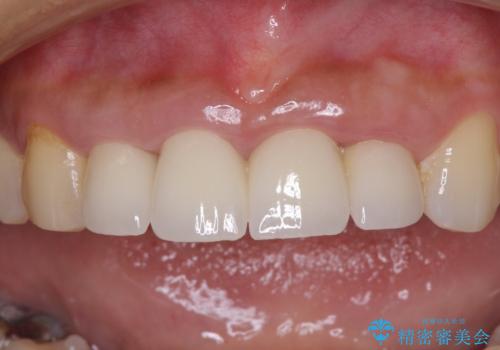

- 地元の歯科医院にて前歯4歯を仮歯に替えたものの、汚れていることが気になるとのことで来院された患者様です。

不適な仮歯の影響で歯肉が腫れていたため、新しい仮歯に替えた後に歯肉の腫れが引くのを待ち、オールセラミッククラウンにて補綴することとしました。

仮歯を変えたことで歯肉の腫れは引き、根管治療も功を奏して膿の出口はきれいに消退しました。